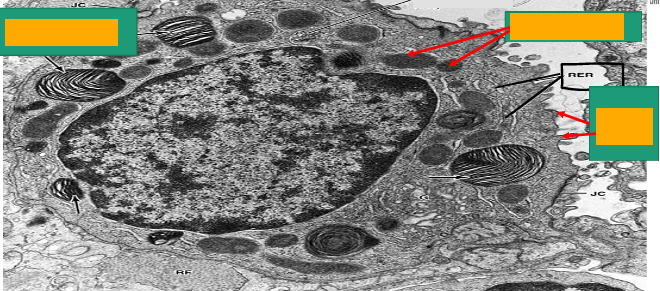

Type II pneumocyte

A -Identify the cell

B -Identify the labelled structure

A- pneumocyte type II

B- Lamellar bodies